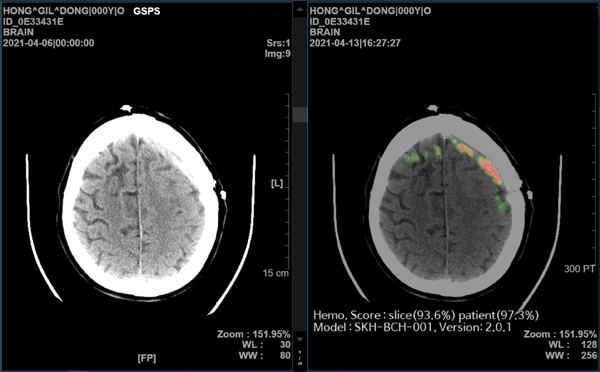

‘메디컬 인사이트 플러스 뇌출혈’은 뇌 CT 영상을 수초 내로 분석해 출혈 위치와 이상 여부를 의료진에게 바로 알려주는 AI 뇌출혈 진단 보조 솔루션이다.

이번 연구에서 비영상의학전문의들이 AI 뇌출혈 진단 보조 솔루션의 도움을 받으면 영상의학전문의 수준의 진단 결과 정확도를 얻을 수 있다는 점이 입증됐다.

의료진을 전공별로 ▲비영상의학전문의 ▲영상의학전문의 ▲신경두경부 영상의학전문의 그룹으로 나누어 AI가 뇌출혈 진단에 미치는 영향을 분석한 결과, 모든 그룹에서 AI의 도움을 받았을 때 진단 정확도의 향상을 보였다.

메디컬 인사이트 플러스 뇌출혈이 의료 기관별로 사용하는 다양한 CT장비 영상을 높은 수준의 정확도로 일관되게 분석한다는 점 또한 확인됐다.

한국지능정보화사회진흥원에서 구축한 약 5만명의 환자 데이터를 대상으로 메디컬 인사이트 플러스 뇌출혈의 AI 자체 진단 성능을 검증했을 때, GE, 필립스(Philips), 지멘스(Siemens), 도시바(Toshiba) CT 장비 모두에서 98~99%의 높은 진단 정확도를 보여줬다.